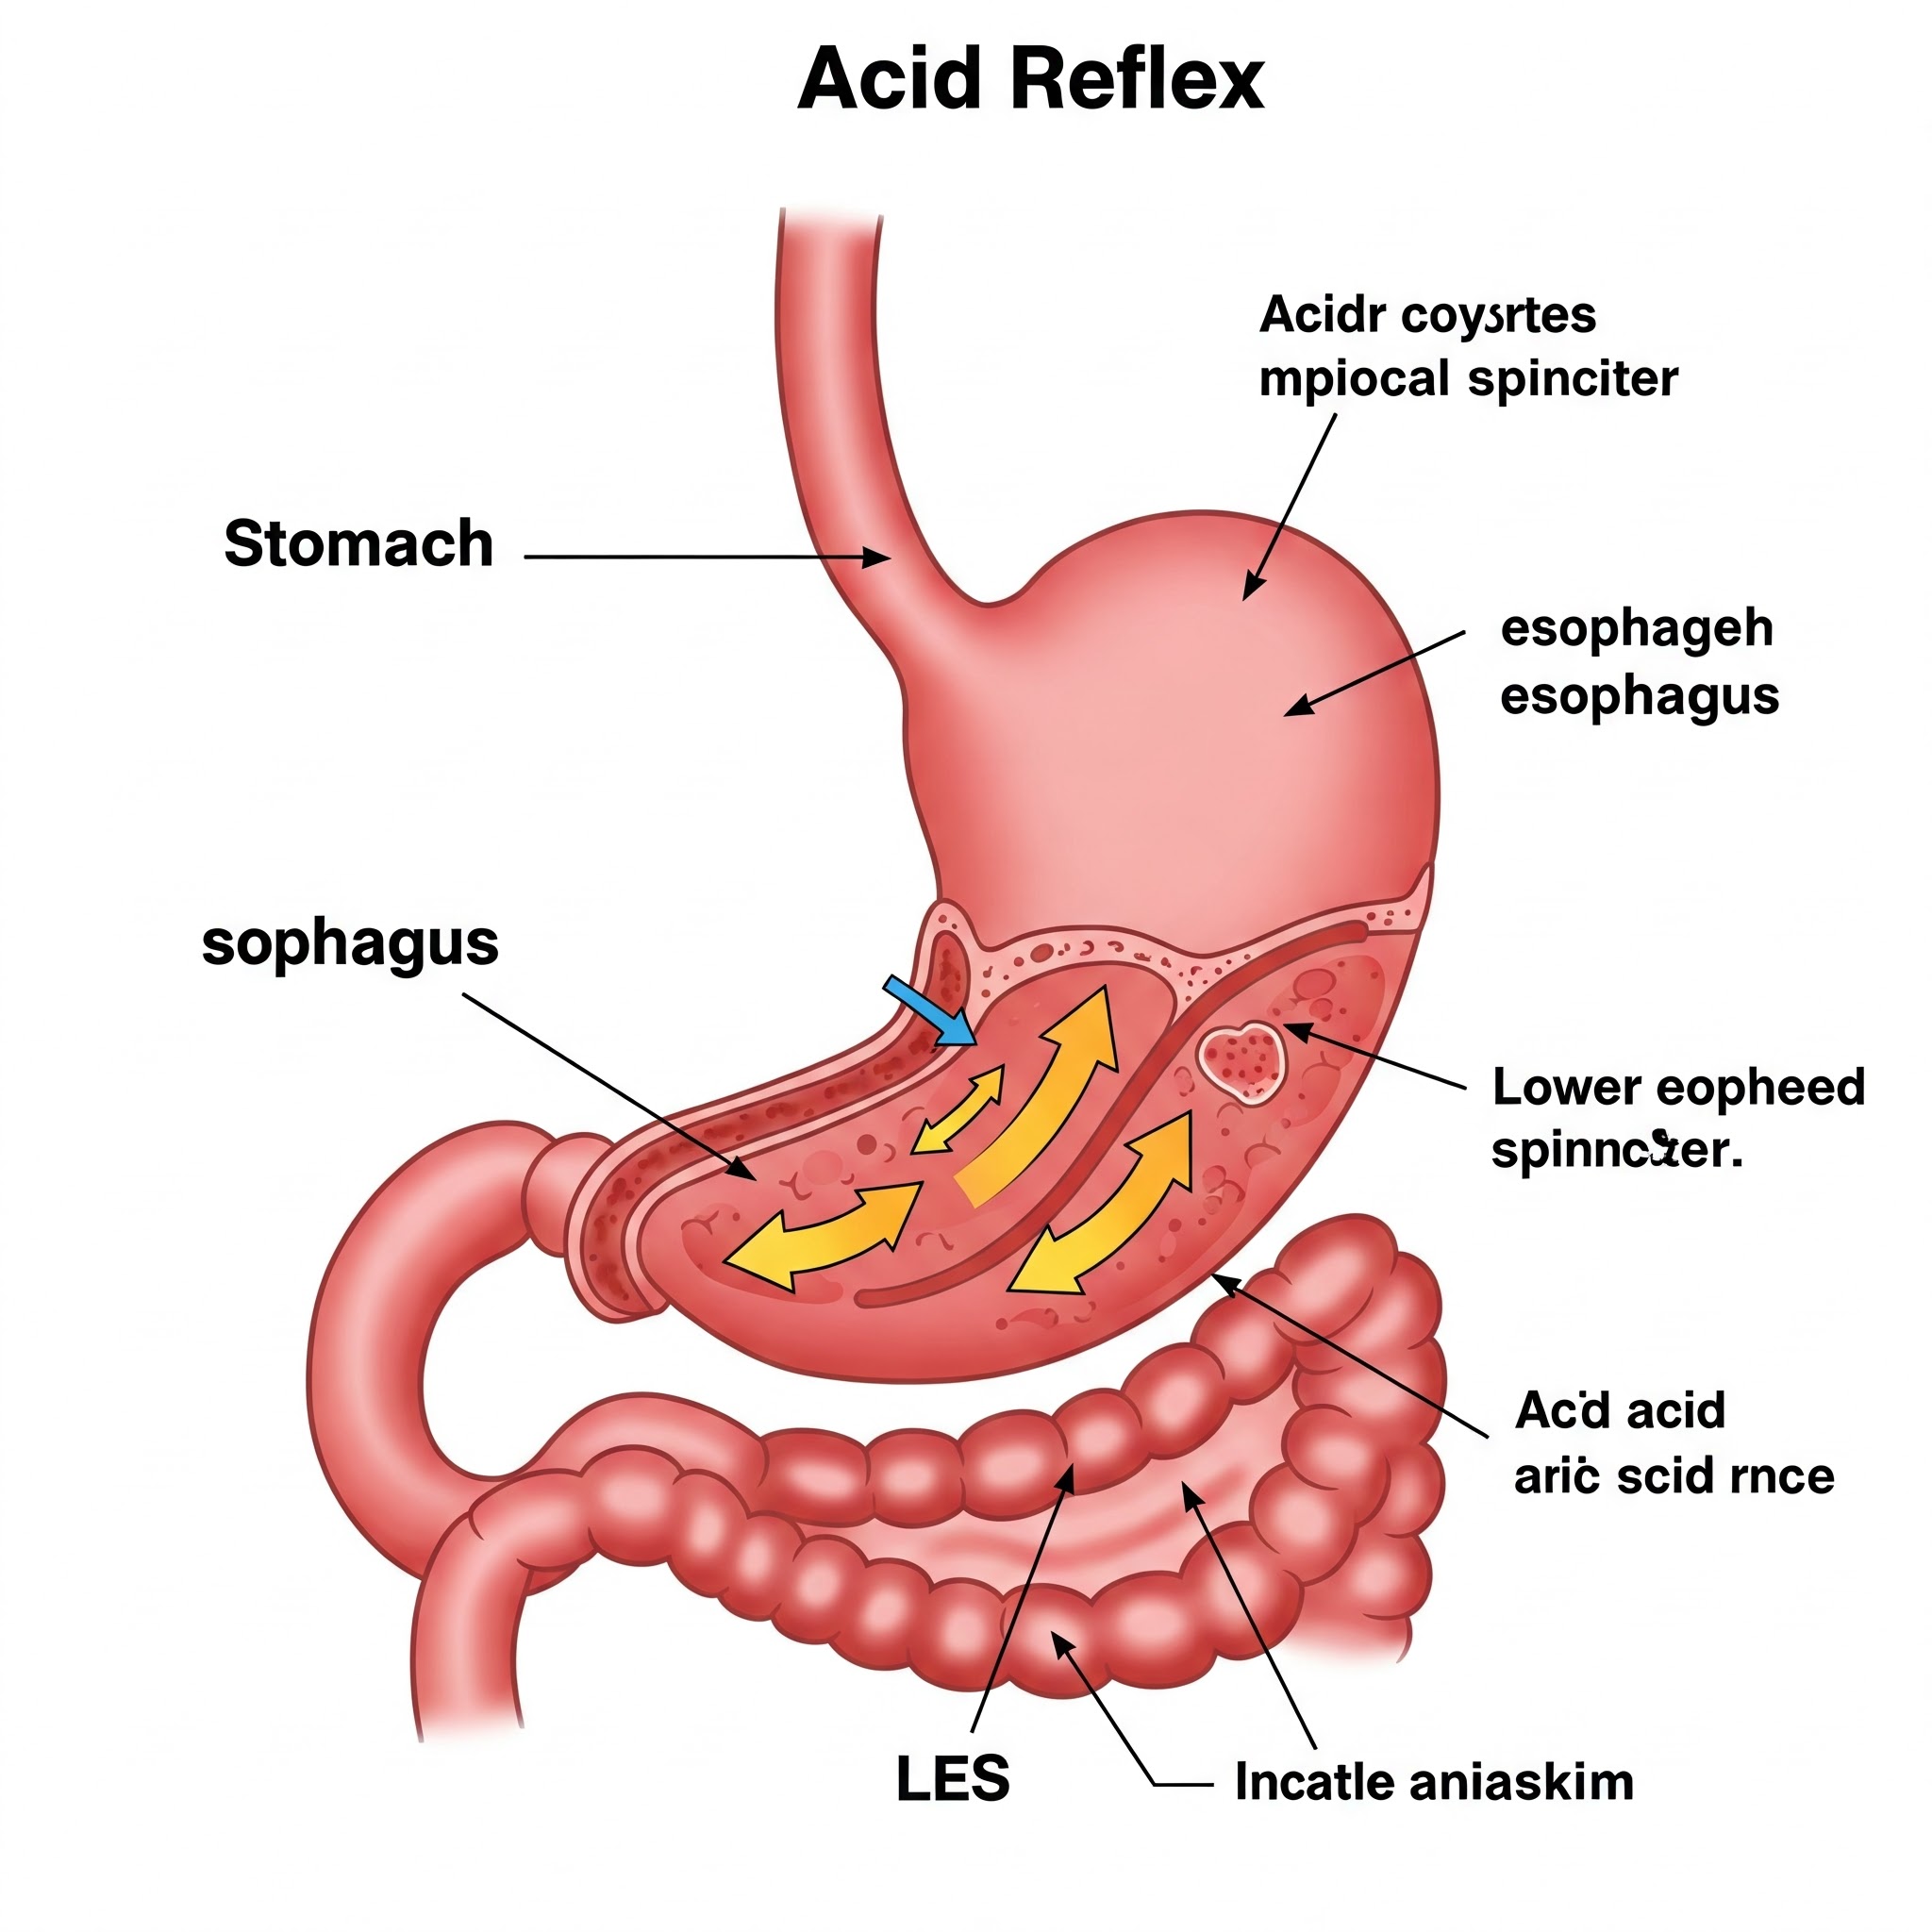

3.3. 위식도 역류질환 (GERD): 주로 오랫동안 흡연 을 하신 분들에게 나타나는 만성적인 호흡기 질환입니다. 기관지와 폐포가 손상되어 기침, 가래, 호흡곤란 등의 증상이 지속적으로 나타나며, 시간이 지날수록 증상이 점점 심해지는 특징이 있습니다. 마치 오래된 파이프가 막히고 손상되어 기능이 떨어지는 것과 비슷하다고 생각하시면 됩니다. 폐기종 과 만성 기관지염 이 COPD에 포함됩니다.

위식도 역류질환: 식이 조절(기름진 음식, 카페인, 탄산음료 피하기)과 함께 위산 억제제 를 사용하여 위산 역류를 막고 식도 염증을 치료합니다.